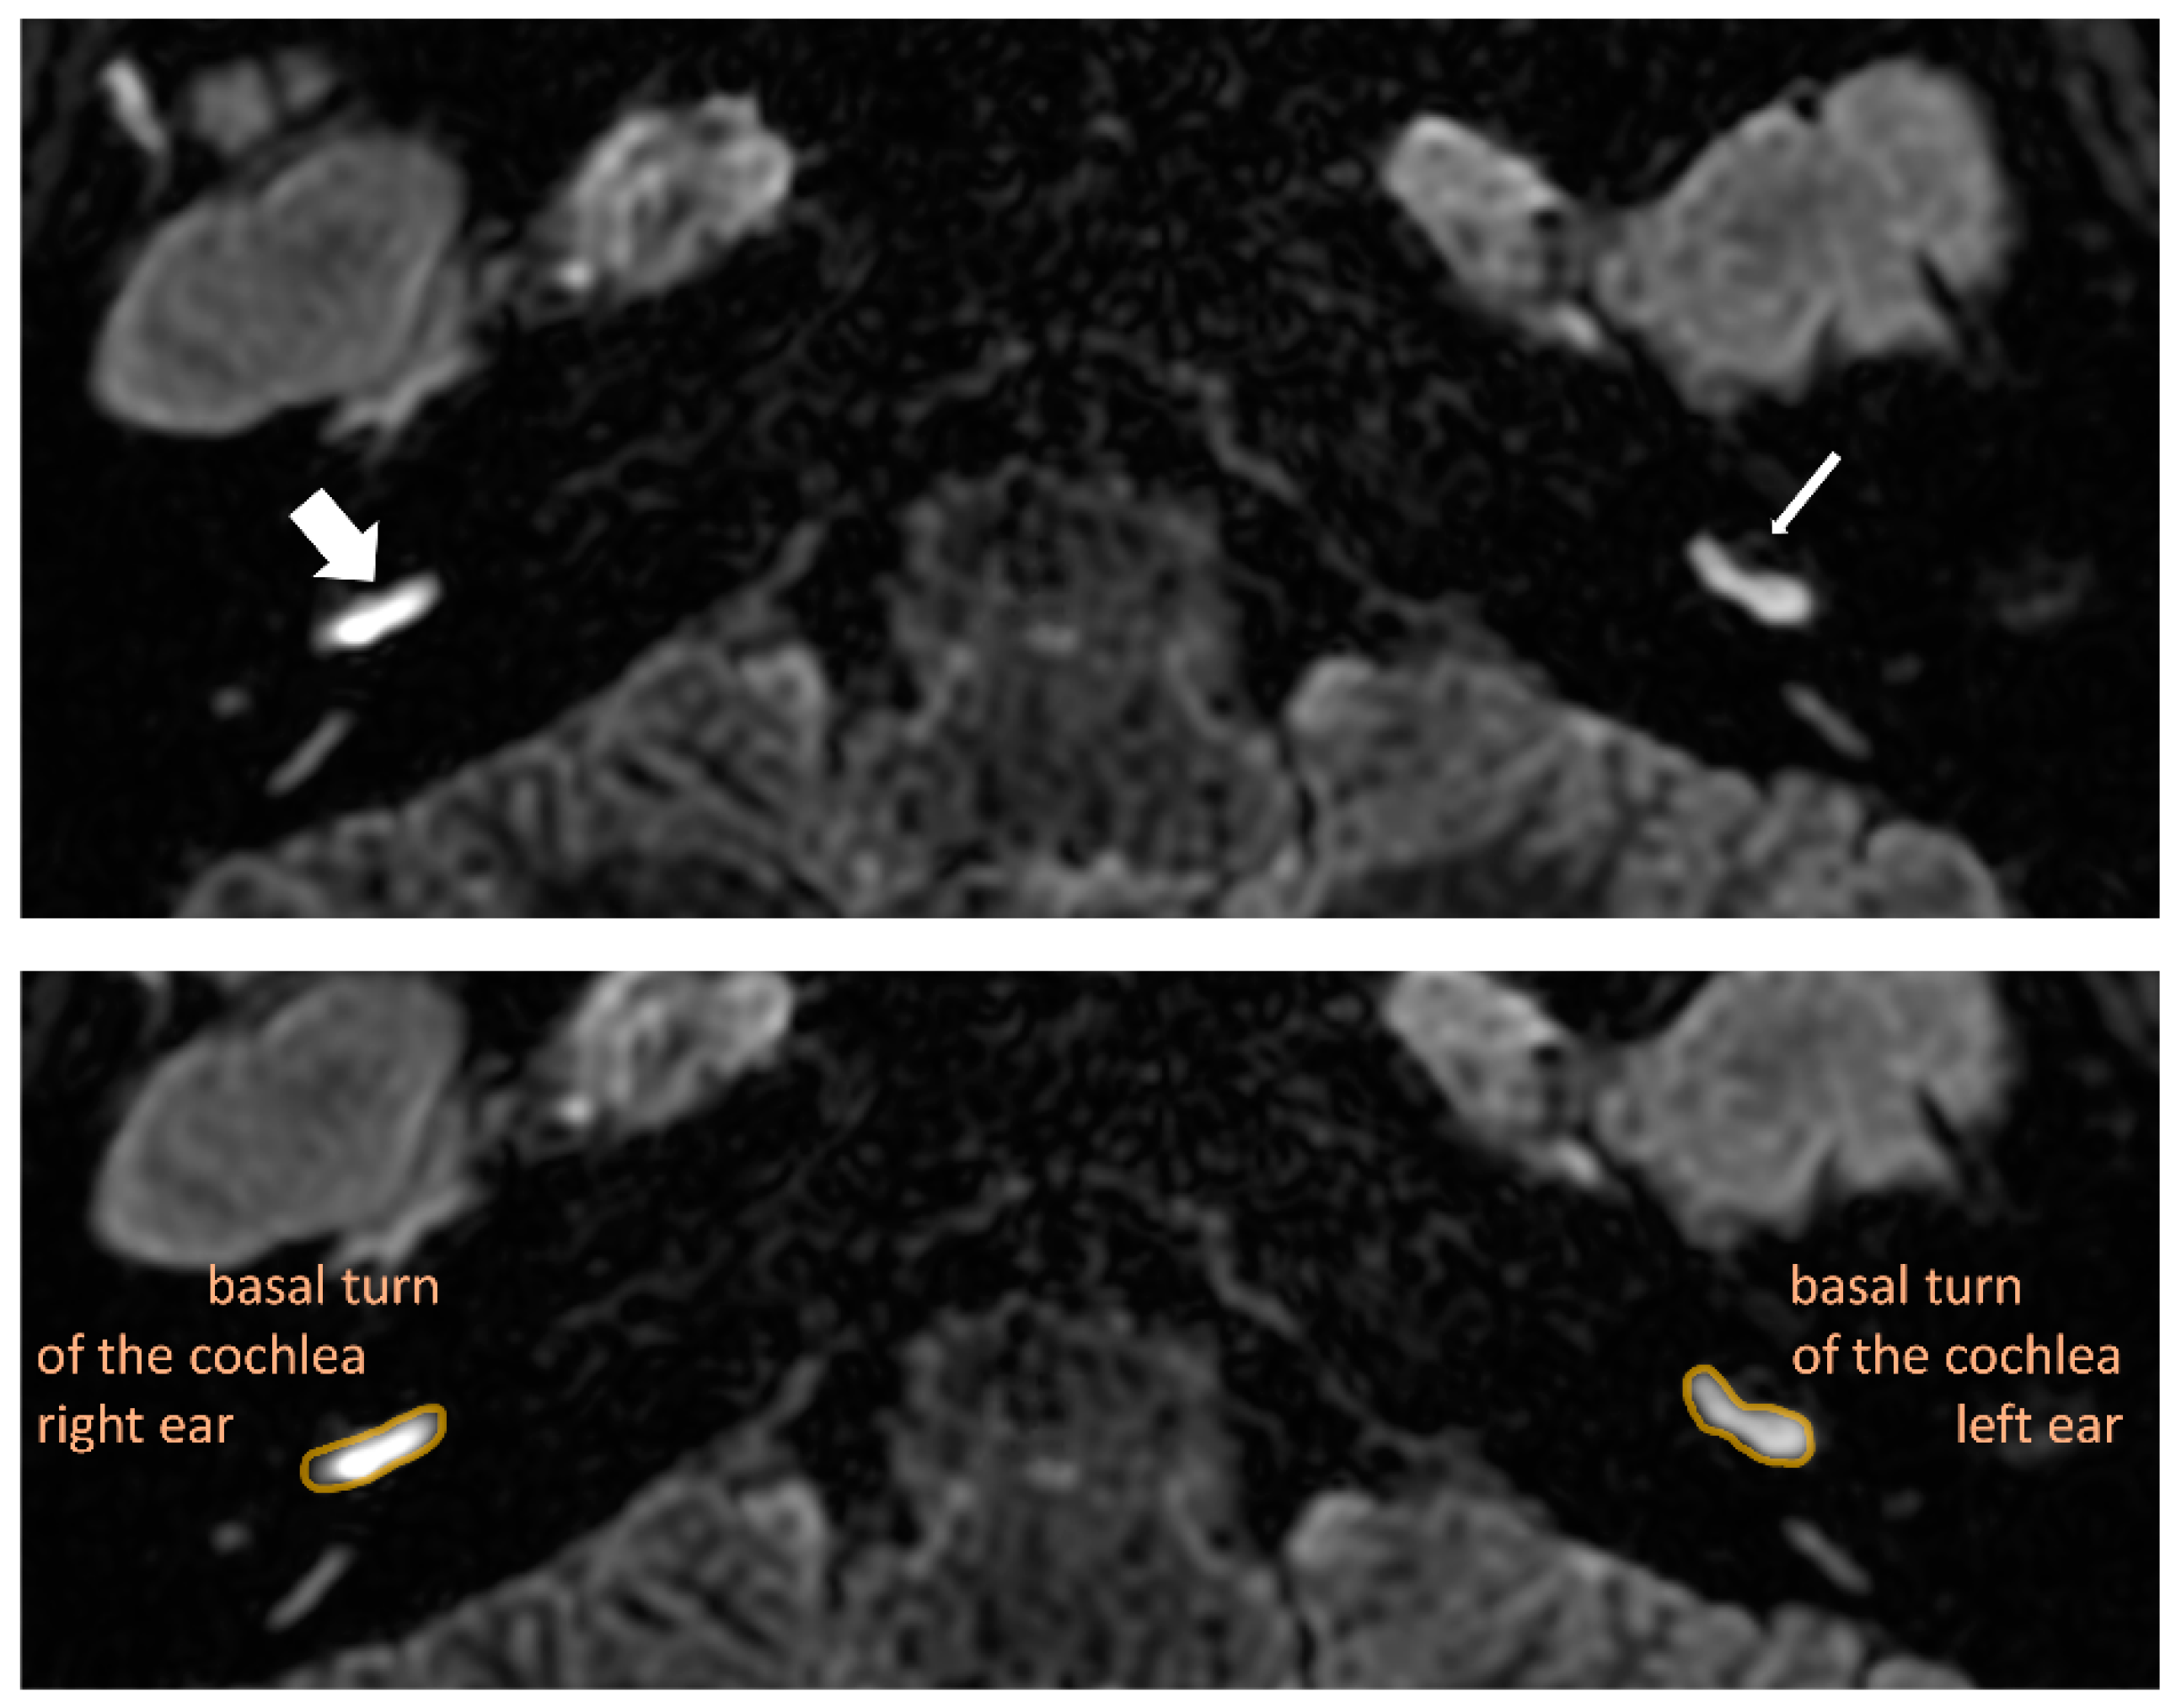

- Barath, K.; Schuknecht, B.; Naldi, A.M.; Schrepfer, T.; Bockisch, C.J.; Hegemann, S.C. Detection and grading of endolymphatic hydrops in Meniere disease using MR imaging. AJNR Am. J. Neuroradiol. 2014, 35, 1387–1392. [Google Scholar] [CrossRef]

- Nakashima, T.; Naganawa, S.; Pyykko, I.; Gibson, W.P.; Sone, M.; Nakata, S.; Teranishi, M. Grading of endolymphatic hydrops using magnetic resonance imaging. Acta Otolaryngol. Suppl. 2009, 129, 5–8. [Google Scholar] [CrossRef]